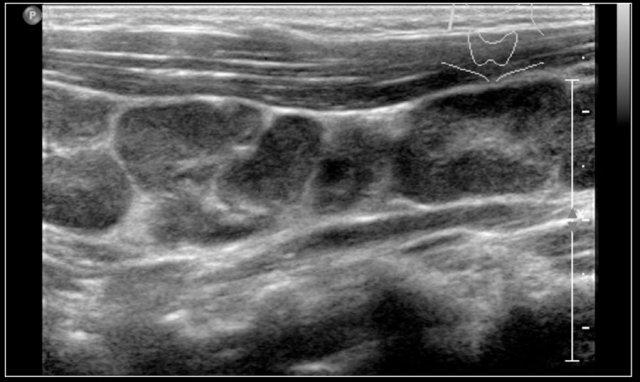

Những hình ảnh này là của một khối u chắc ở cổ của một cô gái 17 tuổi.

Kết quả lấy mẫu tế bào học không có kết luận rõ ràng.

Siêu âm cho thấy hình ảnh điển hình của u vôi hóa biểu mô lành tính (pilomatrixoma), được xác nhận bằng giải phẫu bệnh sau khi cắt bỏ.

Some perfusion in the wall of the pilomatrixoma is seen.